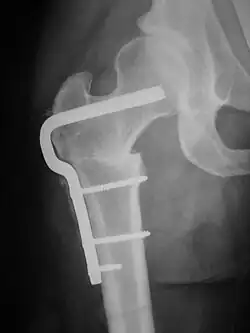

X-ray of Femoral Osteotomy hardware to correct femoral rotation caused by hip dysplasia. X-ray of the right hip in female patient in early thirties.

A femoral derotation osteotomy can be performed to correct version abnormalities such as excessive anteversion or retroversion of the hip joint. Excessive anteversion of the femur results in anterior instability of the hip joint while excessive retroversion results in femoroacetabular hip impingement.[5]

A subtrochanteric blade plate or an intramedullary rod can be used to stabilize the osteotomy site in a femoral derotation osteotomy until compete bone healing is achieved; an approach employing an intramedullary rod is much less invasive than one using a subtrochanteric blade plate.}